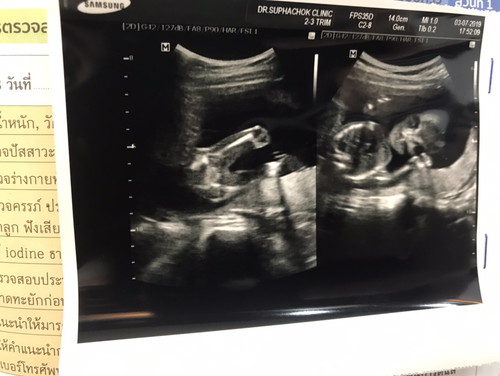

ได้ลูกสาววววว

18 วีค 1 วัน วันนี้คุณหมอบอกว่าคุณได้ลูกสาว ดีใจมากๆค่ะ... กำหนดคลอด ธ.ค. แม่บ้านไหนกำหนดคลอด ธ.ค. บ้างค่ะ เตรียมตัวยังไงบ้างค่ะ ควรเริ่มซื้อของช่วงไหน แนะนำด้วยค่ะ มือใหม่ค่ะ